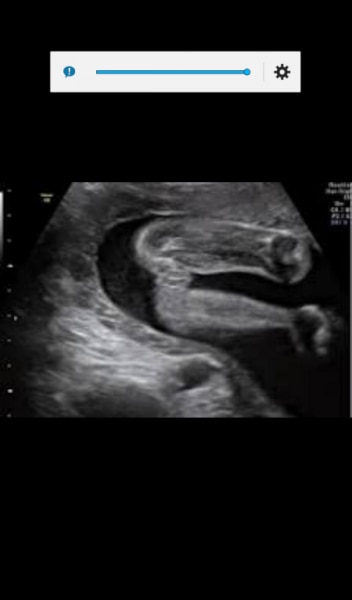

Hallo ihr Lieben! Bisher habe ich hier immer nur fleißig gelesen, aber nie selbst geschrieben. Nun habe ich aber doch eine Frage und bitte um eure Einschätzung :-) Ich war am Freitag bei 18+6 zum Ultraschall. Als ich zu Hause war habe ich ein Bild vom Geschlecht des Kindes entdeckt (rechts Popo, als wenn es auf einem Kopierer säße, links die Beine). Während der Untersuchung hat die Ärztin sich diesbezüglich überhaupt nicht geäußert. Was meint ihr, sieht man auf dem Bild einen Jungen oder ein Mädel? https://www.dropbox.com/s/ypqmqptrvsce53i/2014-12-31%2007.52.23.jpg?dl=0 Herzlichen Dank und liebe Grüße!

ich tippe vorsichtig auf Junge aber so eindeutig ist das nicht finde ich

Lieben Dank für deine Einschätzung. Ich hätte auch auf Junge getippt, finde es aber auch nicht deutlich! Hat noch jemand einen Tipp? ☺

Hey! Könnte Hodensack oder Schamlippen sein. Ich tippe auf Mädchen. LG

Ich würde auch auf Junge tippen. So sah das bei meinem Sohn auch aus.

ich seh ein mädchen.. ich kann keinen penis erkennen, dafür aber den spalt zwischen den schamlippen

ich sehe einen Jungen

Ich sehe die 2 hodensäcke (die im übrigen auch unten zusammen gehen) und dann dazwischen den Penis. Für mich sieht es nach 3 teilen aus. Ja die Vulva ist geschwollen, aber eben auch der hodensack. Und bei uns war zwischen den schamlippen immer ein strich. Den sehe ich hier nicht. Darum rippe ich auf junge.

Dr. Bluni findet es nicht eindeutig, tendiert aber zu nem Jungen. Ich halte euch auf jeden Fall auf dem Laufenden, aber leider dauert es noch drei Wochen bis zum nächsten Termin...

Ihr Lieben, vielen Dank nochmal für eure Einschätzungen. Nun des Rätsels Lösung: Der letzte Ultraschall hat ergeben, dass wir einen kleinen Jungen bekommen :-) Liebe Grüße